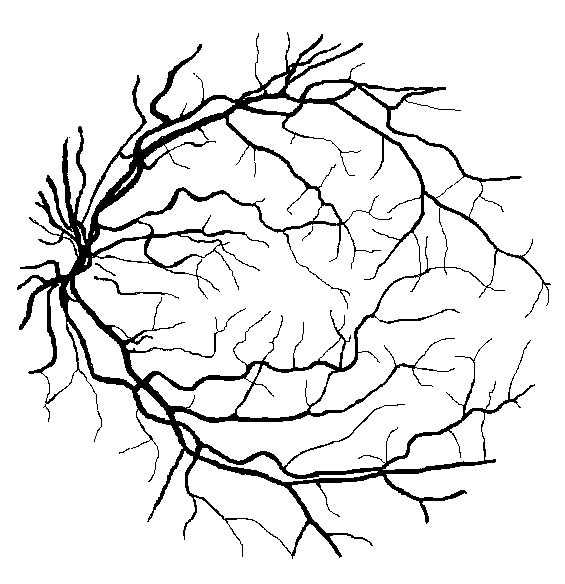

A particularly popular problem in retinal image analysis is the segmentation of retinal vessels (illustrated in Figure 1). The importance of the problem is threefold. On the one hand, the characteristics of the vasculature can aid the early detection of diseases like hypertension (lui Cheung et al., 2012). On the other hand, the removal of vessels usually precedes the detection of other anatomical parts. For example, the high curvature and junction points of thin vessels have similar visual features to microaneurysms (Long et al., 2020), consequently, the segmentation of the vasculature can indirectly aid the detection of mycroaneurysms. Finally, the segmented vasculature may serve as a guide for locating other anatomical parts, such as the macula (Yu et al., 2014).

The Digital Retinal Images for Vessel Extraction (DRIVE) data set (Niemeijer et al., 2004) contains 20 training and 20 test entries. Images were captured with a Canon CR5 non-mydriatic 3CCD camera with a 45 degree field of view and cropped to 584565 pixels. Each training entry consists of a retinal image, a binary annotation of vessels (by annotator #1), and a binary mask of the Field of View (FoV) indicating the useful image content. The FoV masks cover 69% of the rectangular images. Each test entry includes an additional manual segmentation by annotator #2, enabling the evaluation of human annotators as a baseline. A complete entry from the test set is visualized in Figure 1.